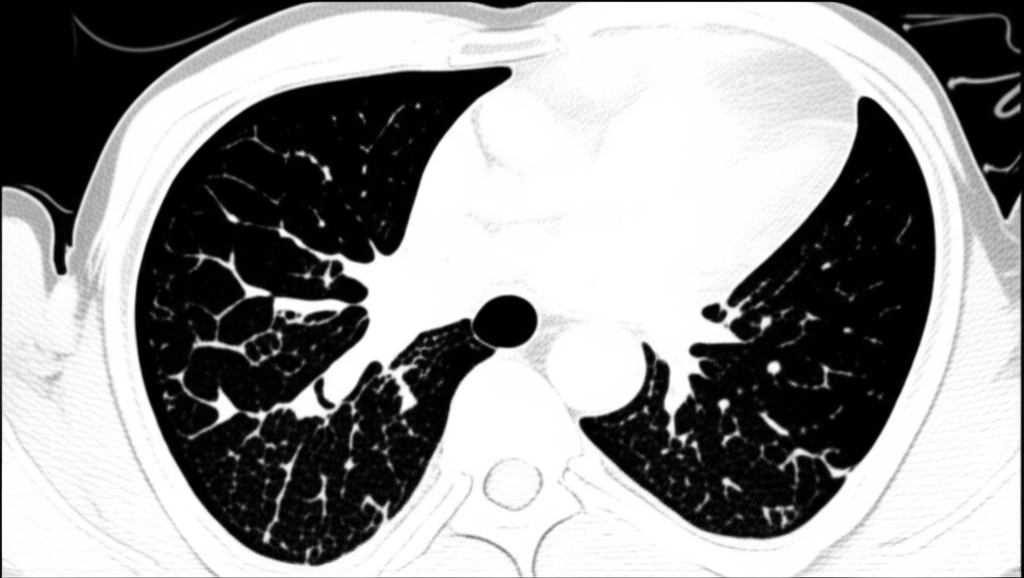

폐 CT로 알 수 있는 것은 폐암뿐만 아니라 폐렴, 결핵, 기관지확장증, 간질성 폐질환 등 다양한 폐 질환을 진단하는 데 유용합니다. 이러한 질환들은 호흡 곤란, 기침, 가래 등의 증상을 유발할 수 있으며, 심한 경우 생명을 위협할 수도 있습니다. 폐 CT 검사를 통해 이러한 질환들을 조기에 발견하고 적절한 치료를 받으면 질병의 진행을 늦추고 합병증을 예방할 수 있습니다.

폐 CT는 COPD 환자의 폐기종 정도, 기관지 확장 여부, 폐렴 발생 여부 등을 평가하는 데 사용됩니다. 이를 통해 COPD의 진행 정도를 파악하고, 적절한 치료 계획을 수립하여 환자의 삶의 질을 향상시킬 수 있습니다.

폐 CT는 간질성 폐질환의 종류와 범위를 파악하고, 질병의 진행 정도를 평가하는 데 중요한 역할을 합니다. 간질성 폐질환은 폐 섬유화를 유발하여 호흡 곤란을 악화시킬 수 있으므로, 폐 CT 검사를 통해 조기에 진단하고 적절한 치료를 받는 것이 중요합니다.